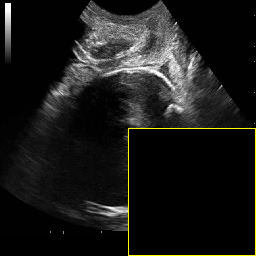

Figure 4 and Figure 5 provide visual comparisons of segmentation masks generated by DAUNet and other competing methods on representative samples from both datasets. As illustrated in Figure 4, DAUNet produces more accurate and smoother boundary delineations, closely aligning with the ground truth annotations, even in challenging low-contrast regions or under partial occlusion. A similar performance can be observed in Figure 5, where proposed model accurately identify the pulmonary embolism regions. It is worth nothing that the proposed model achieve best performance in two different imaging modalities, consisting of different sized regions of interest and number of classes demonstrating a good generalization.

In practical clinical settings, medical images are often incomplete or degraded due to occlusions, artifacts, or limited fields-of-view. Therefore, a reliable segmentation model must be robust to missing spatial context and capable of inferring anatomical structures from partially observed inputs. To evaluate this critical property, we conducted a masking experiment using the FH-PS-AoP dataset. In this experiment, we systematically removed one quadrant from the input image, top-left, top-right, bottom-left, or bottom-right, and evaluated the performance of DAUNet compared to the baseline UNet.

Figure 7 presents a comprehensive visual comparison of the predicted offset maps and segmentation masks under each masking condition. The first column shows the original (unmasked) input along with its corresponding predictions, while subsequent columns depict the results for each of the masked quadrants.

DAUNet demonstrates markedly higher resilience to missing context compared to UNet. Its predicted offset maps remain dense and structured, with vectors that preserve anatomical directionality even when significant regions of the input are absent. This behavior reflects DAUNet’s ability to infer context from the remaining visual cues. In contrast, UNet exhibits sparse or disoriented offsets in the masked scenarios, indicating reduced spatial awareness and compromised localization.

To better understand this phenomenon, we analyzed the receptive fields of both models. For a representative pixel, we visualized its corresponding receptive area contributing to the output. In UNet, the receptive field is fixed and grid-constrained (refer to second row of Figure 7), making it sensitive to occlusions. On the other hand, DAUNet leverages deformable convolutions to dynamically adjust its receptive field based on the visible content. This adaptability is evident in the red and white arrows in the fourth column of Figure 7, where DAUNet modifies its offset patterns to account for the masked input.

The segmentation masks in third and fifth rows of Figure 7, further substantiate these findings. DAUNet consistently produces anatomically plausible segmentations of both the fetal head (green) and pubic symphysis (red), with minimal degradation even under 25% missing input. The output contours remain smooth, accurate, and well-aligned with ground truth boundaries. In contrast, UNet’s performance deteriorates noticeably, with fragmented or distorted segmentations, especially around the fetal head, as indicated by white arrows in the figure.

These results highlight the efficacy of DAUNet’s architectural innovations. The proposed combination of deformable convolution and SimAM attention allows the model to effectively reason over the visible context and compensate for spatial omissions. This robustness to incomplete inputs makes DAUNet well-suited for deployment in real-world medical environments, where noise, occlusions, and partial data are common challenges.